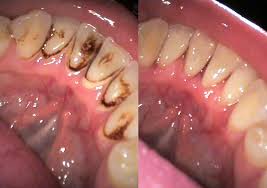

Aqui teneis un video donde se ve como limpiamos el sarro con ultrasonidos.

La limpieza dental tiene como principal objetivo la eliminación del sarro que se acumula en los dientes y que no es posible quitar con las técnicas higiénicas que el paciente se aplica en casa,es decir, con el cepillado de dientes, uso de sedas dentales y cepillos interproximales.

• Limpieza con ultrasonidos: Es este caso el proceso de limpieza dental será más rápido. Se hace mediante una herramienta que produce una vibración que facilita la eliminación de sarro sin dañar el diente y sustituye los instrumentos tradicionales.

El aparato de ultrasonidos viene con una punta curvada que se engancha en un aparato, que vibra y echa agua. Te van pasando esa punta por el relieve de los dientes, haciendo hincapié en las zonas donde no entre bien tu cepillo, en el borde que hay justo entre el diente y la encía.

Esta vibración lo que permite es eliminar el sarro y la suciedad que se ha podido acumular durante pasado los meses hasta tu limpieza dental.

Después de pasar el ultrasonido , se pulen los dientes con una pasta abrasiva y un microcepillo.